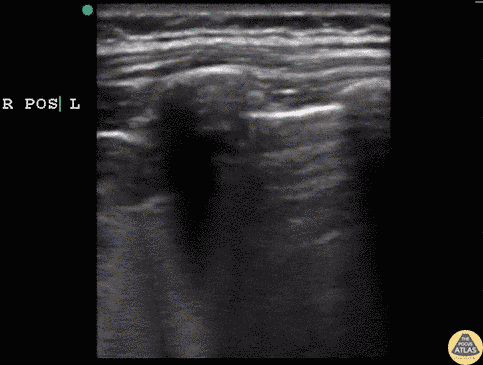

Pediatrics - Hydrocarbon Ingestion with C-Lines

5 year old male that drank out of container with gasoline and started coughing and was breathing fast. On exam appeared tachypneic, with air entry bilaterally and subcostal retractions. POCUS revealed bilateral infiltrates, confirmed with CXR. Infiltrate, similar to C lines seen in other consolidative processes, present in patient post hydrocarbon ingestion. This suggests an aspiration pneumonia. Dr. Sathya Subramaniam, Pediatric EM Fellow - Kings County/SUNY Downstate